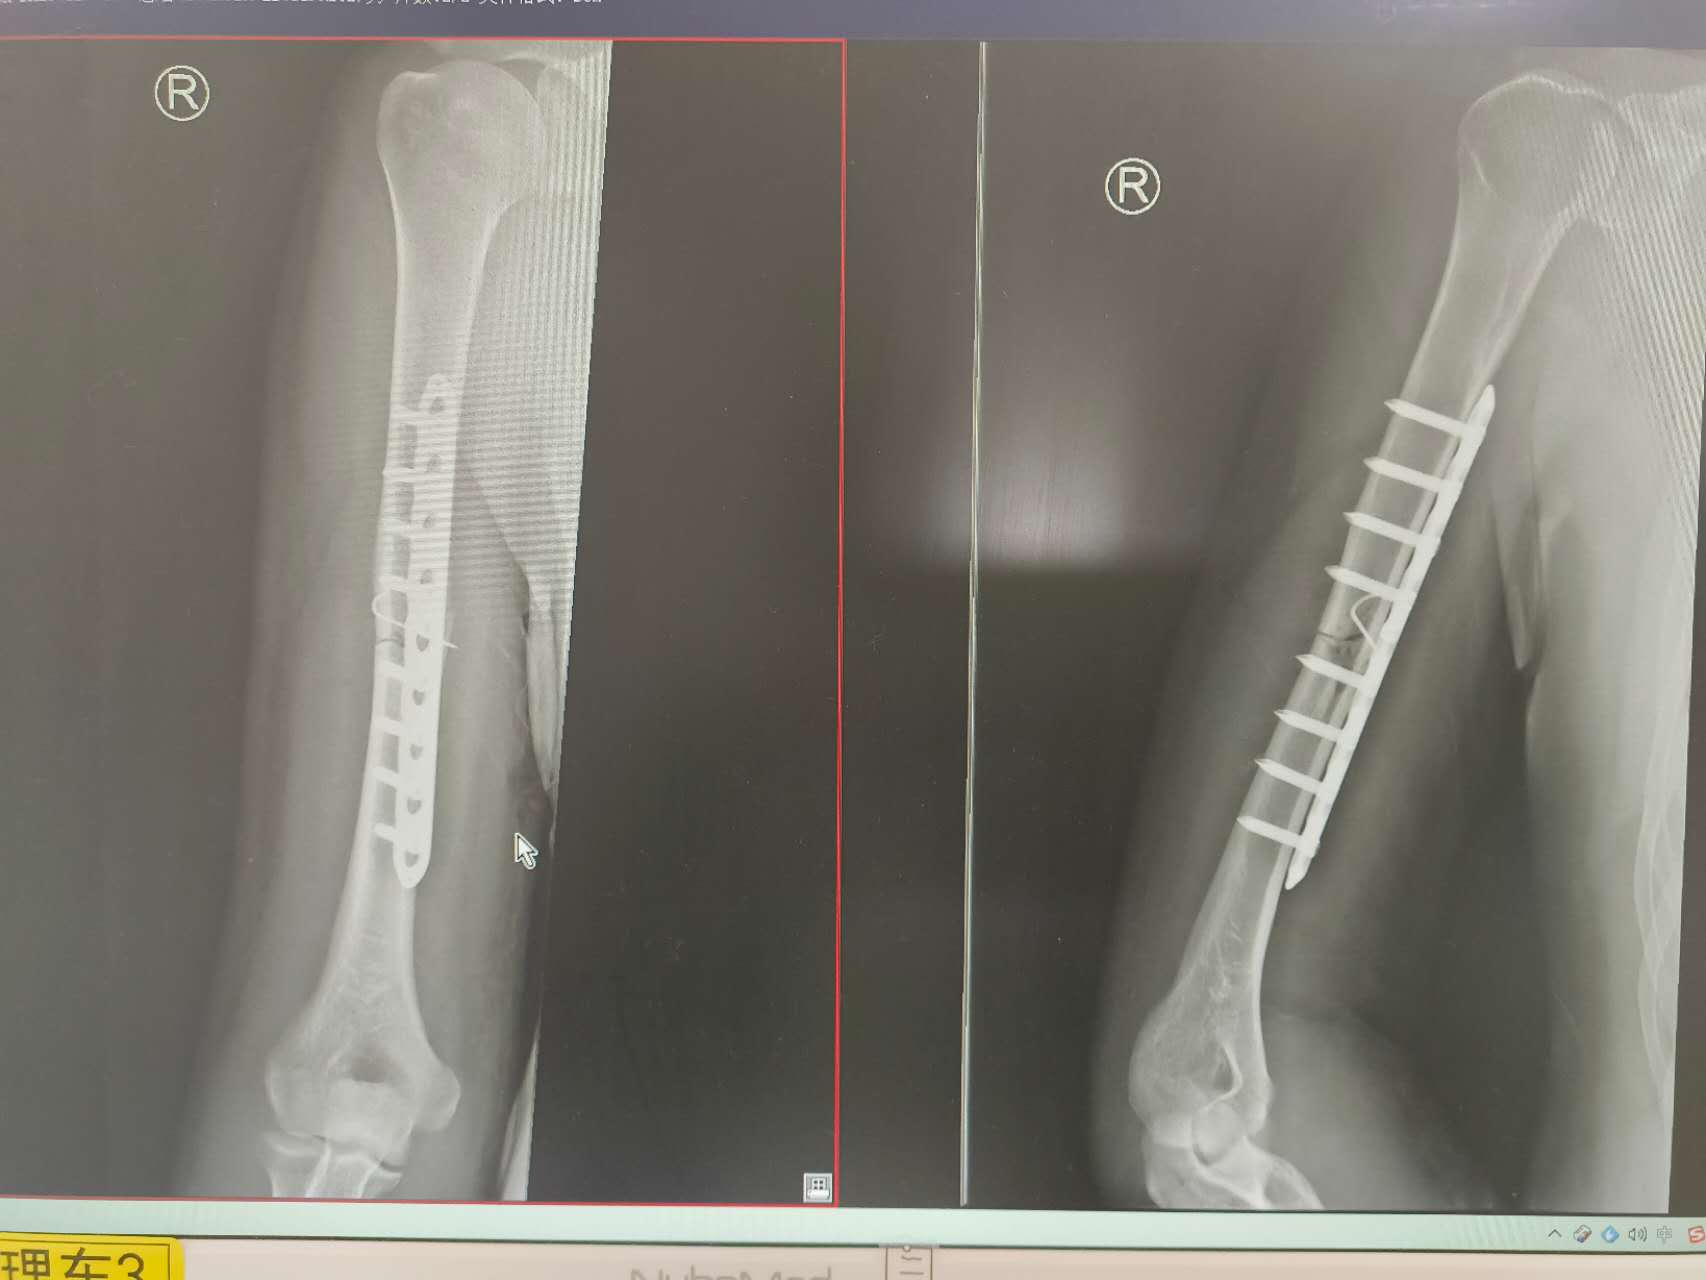

The surgery happened Thursday afternoon and took under three hours. Before I went under, I patiently reminded my surgeons that it was the right arm that needs the business, and then I laid there humming the Wong Fei Hung themesong (lyrics / version by Jackie Chan / the best version of all) until the anaesthesia kicked in.

When I woke up I knew the surgery had been a success: structural integrity restored.

I dangle no more.

8 screws and an impressive (titanium?) rod makes me whole. I am told I can have another surgery in a year or so to remove the rod, but unless someone explains to me a medical reason why removing the rod is necessary, I see no reason to undo the first step of my transhuman evolution into wolverine.